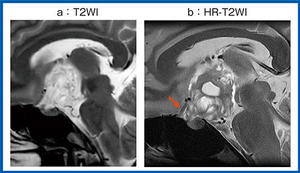

第52回日本磁気共鳴医学会大会ランチョンセミナー5 DLR-MRIの進歩と今後の可能性

(2025年5月号)

AIと4D Flowで解き明かす心動態の次の一手

真鍋 徳子(自治医科大学附属さいたま医療センター放射線科)